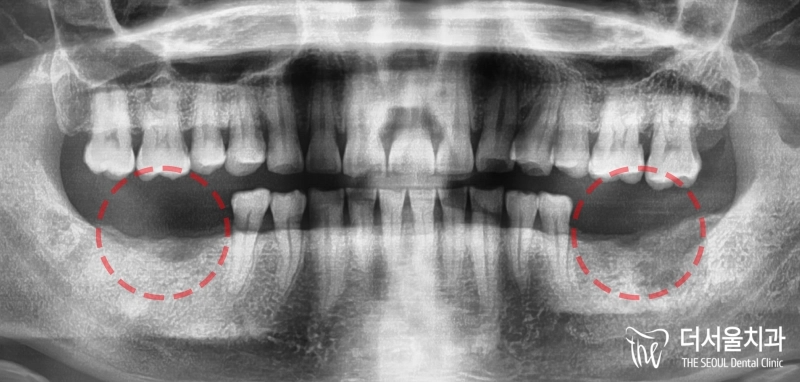

반갑습니다. 잠실 더서울 치과 입니다. 오늘 소개해 드릴 사례는 예전에 찾아오셔서 좌측 아래 어금니 임플란트 식립을 받으셨던 환자분께서 우측